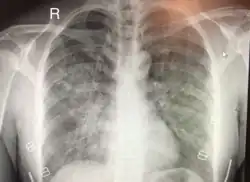

Chest x-ray of HAPE showing characteristic patchy alveolar infiltrates with right middle lobe predominance. | |

On physical exam, increased breathing rates, increased heart rates, and a low-grade fever 38.5o C (101.3o F) are common.[9][3] Listening to the lungs may reveal crackles in one or both lungs, often starting in the right middle lobe.[9][3] Imaging studies such as X-ray and CT imaging of the chest may reveal thoracic infiltrates that can be seen as opaque patches.[14][9][3] One distinct feature of HAPE is that pulse oximetry saturation levels (SpO2) are often decreased from what would be expected for the altitude. People typically do not appear as ill as SpO2 and chest X-ray films would suggest.[9][3] Giving extra oxygen rapidly improves symptoms and SpO2 values; in the setting of infiltrative changes on chest X-ray, this is nearly pathognomonic for HAPE.[3]